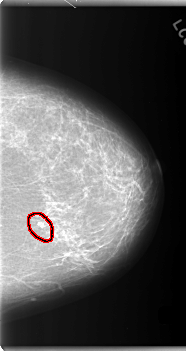

C_0106_1.LEFT_MLO

LEFT_MLO LINES 5904 PIXELS_PER_LINE 3384 BITS_PER_PIXEL 12 RESOLUTION 50 OVERLAY

FILE: C_0106_1.LEFT_MLO.OVERLAY

TOTAL_ABNORMALITIES 1

ABNORMALITY 1

LESION_TYPE CALCIFICATION TYPE PLEOMORPHIC DISTRIBUTION CLUSTERED

ASSESSMENT 4

SUBTLETY 5

PATHOLOGY MALIGNANT

TOTAL_OUTLINES 1

BOUNDARY